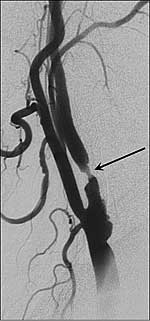

Bildunterschrift: Röntgendarstellung der Halsschlagader. Der Pfeil markiert die Einengung der Halsschlagader durch Plaque (Kalkablagerung).

Bildquelle: Universitätsklinikum Heidelberg